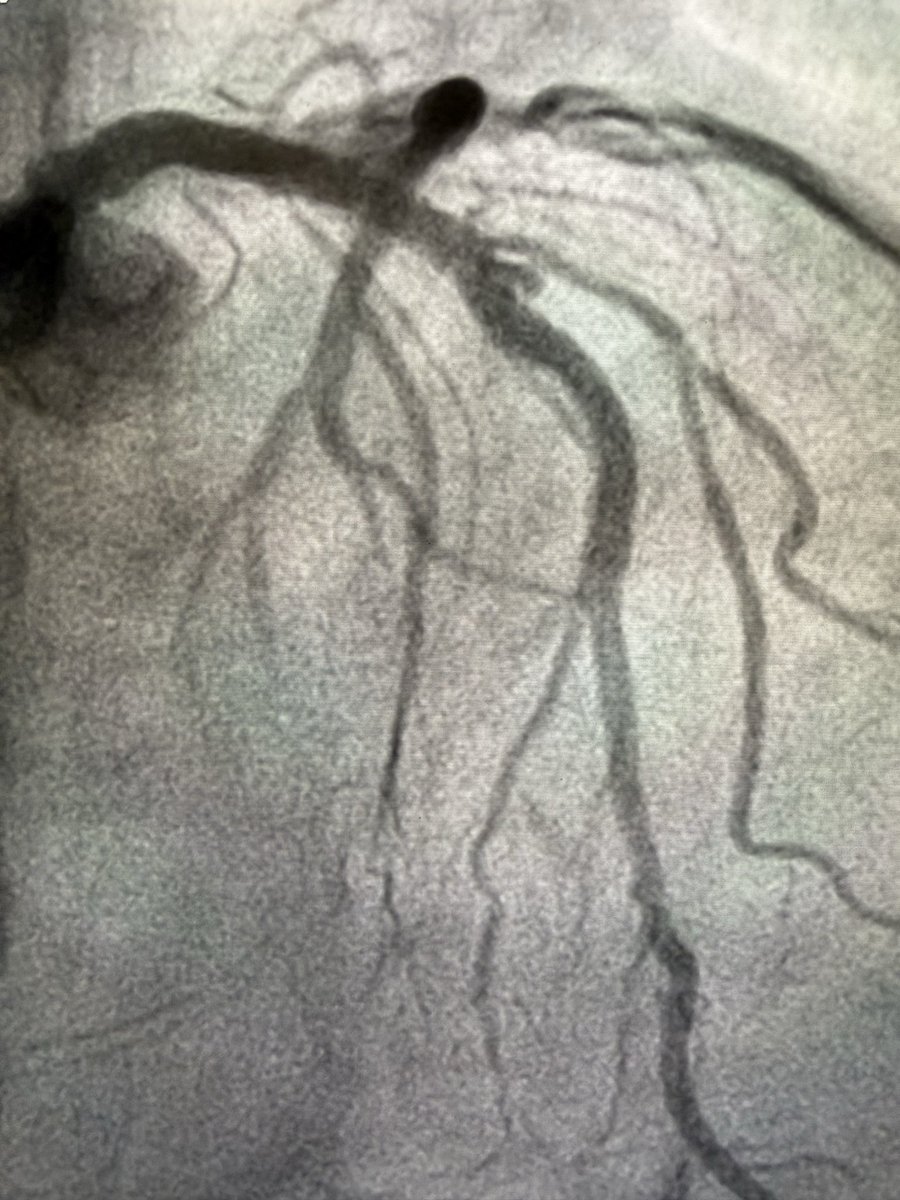

@AdityaMandawat DES across it and no change to DAPT duration. No anticoagulation for these smaller aneurysmal lesions